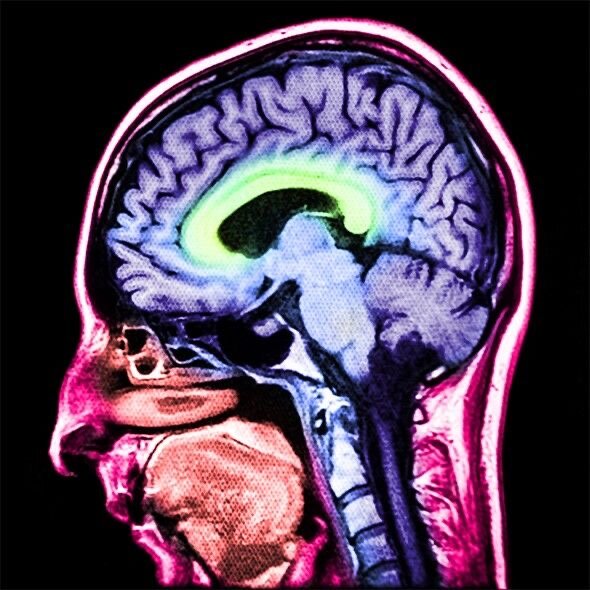

Что делать, если вы или ваш близкий получили черепно-мозговую травму?